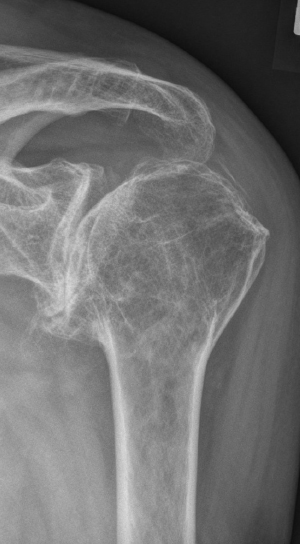

Pre-op

- 73-year-old female patient

- Omarthrosis

- Cuff tear arthropathy

- Reduced bone quality

- Suffering from pain for many years

- Limited elevation and rotation